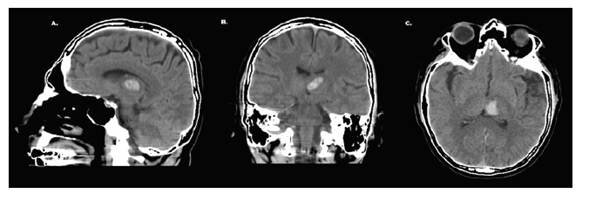

Por tratarse de un cuadro con compromiso neurológico, se solicitó valoración por el Departamento de Neurología y Neurocirugía, que valoran al paciente, quien evidenció cuadro clínico similar a las anotaciones en la exploración física y paraclínica previa; se describió TAC con hallazgos compatibles con hemorragia intraparenquimatosa en la región talámica izquierda (figura 1: A, B y C), por lo que se amplió el estudio y se solicitó ecografía de vasos carotideos, Resonancia Magnética Nuclear (RMN) de cerebro contrastada y panangiografía cerebral.

Se reporta ecografía de vasos carotideos sin compromiso hemodinámico cerebral. La RMN evidenció hematoma intraparenquimatoso de ubicación talámico-izquierda (figura 2). La panangiografía cerebral no reveló hallazgos patológicos. Se decide un tratamiento conservador y monitorización neurológica. Transcurrido el tercer día de hospitalización, el paciente recuperó la totalidad de sus funciones neuropsicológicas sin secuelas. Durante los siguientes tres días de hospitalización el paciente continuó su evolución de manera satisfactoria. Se dio de alta médica con recomendaciones y manejo sintomático. No obstante, continúa en seguimiento periódico por parte del Departamento de Neurología.